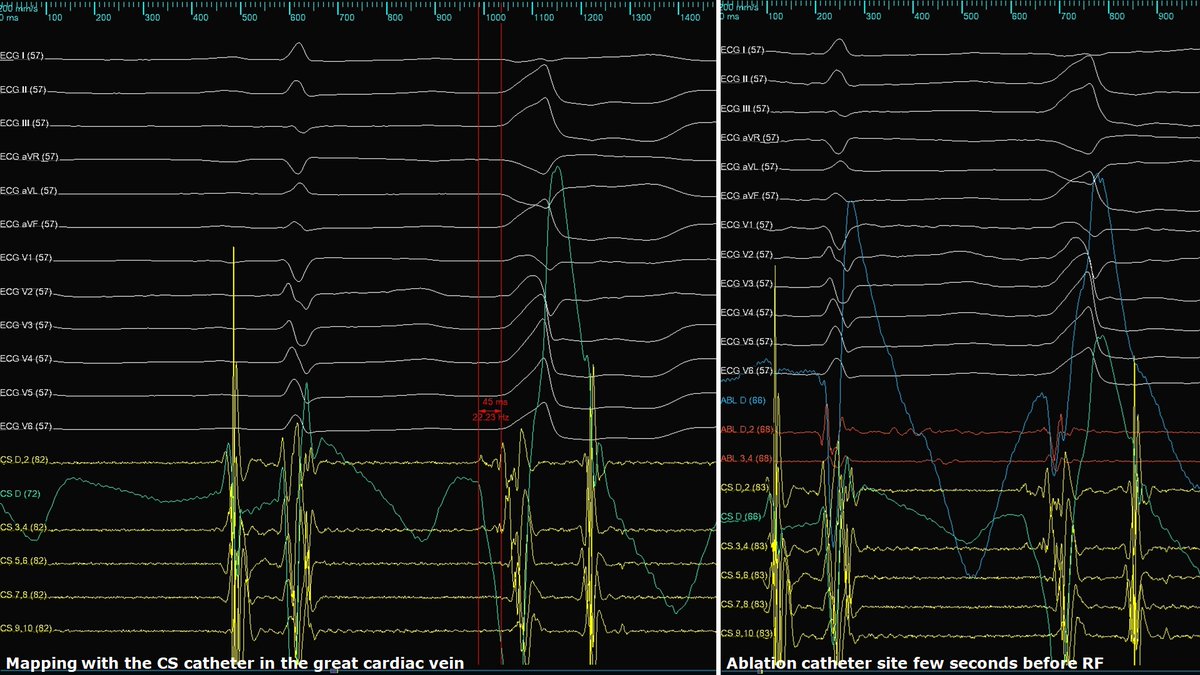

Celebrating 1yr since the publication of our Atlas of ConductSystemPacing #LBBAP #HBP! Thanks @ilpensiero for their support & to the readers for their trust! I hope it has been (& will be) useful to become confident in recognizing #CSP in your procedures! tinyurl.com/CSPAtlas